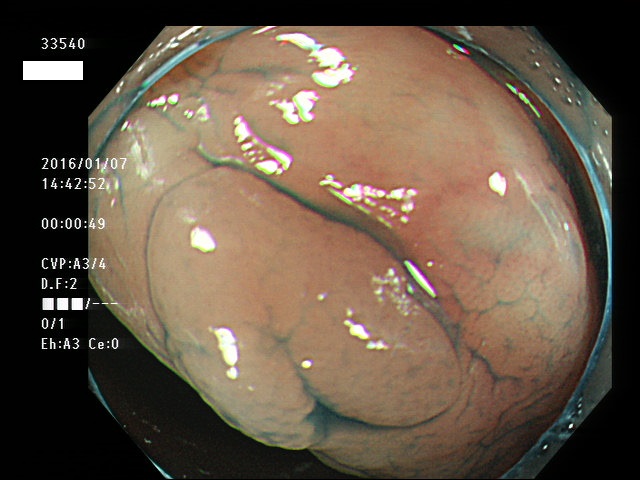

上記100名より抽出した平坦・陥凹型腺腫(=癌化の危険が高いが見落としやすい病変)の内視鏡写真

33500 33501 33505 33507 33508 33509 33510(SSA/Pのみ) 33511 33512 33514 33517 33519 33523 33528 33529 33530 33535 33537 33538 33539 33540 33544 33546 33547 33548 33549 33550 33552 33553 33555 33558 33559 33562 33563 33567 33571 33576 33578 33580 33581 33583 33585 33586 33587 33589 33590 33594 33595 33596 33599 ・・・・・・の50名